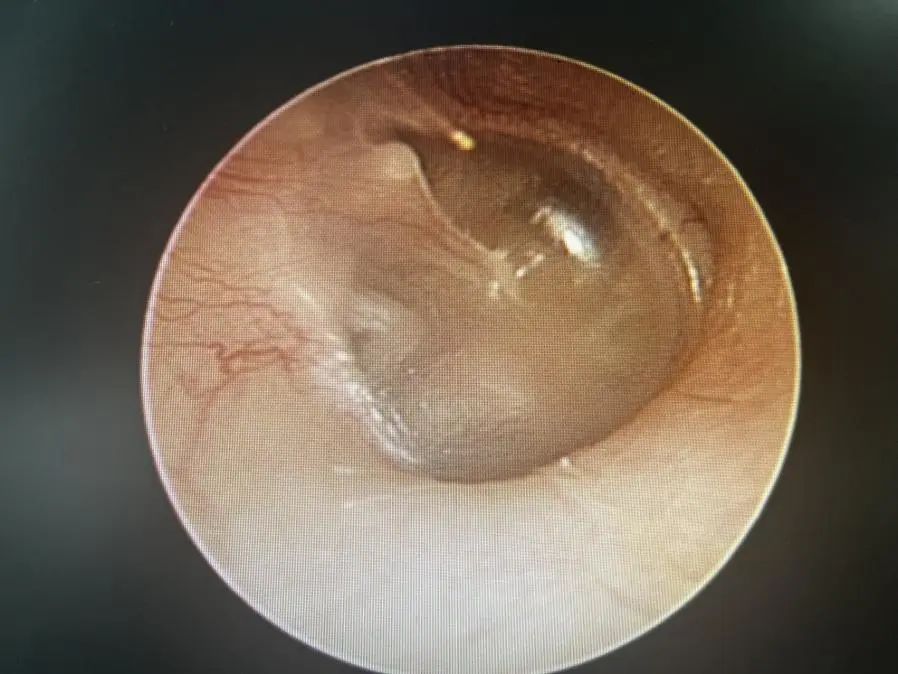

醫(yī)生在視頻耳內(nèi)鏡下發(fā)現(xiàn)左側(cè)鼓膜有一個破口,有血跡殘留在鼓膜上,還做了純音聽閾檢測,檢查結(jié)果顯示,小花的左耳聽力呈中度傳導性耳聾。

鼓膜穿孔